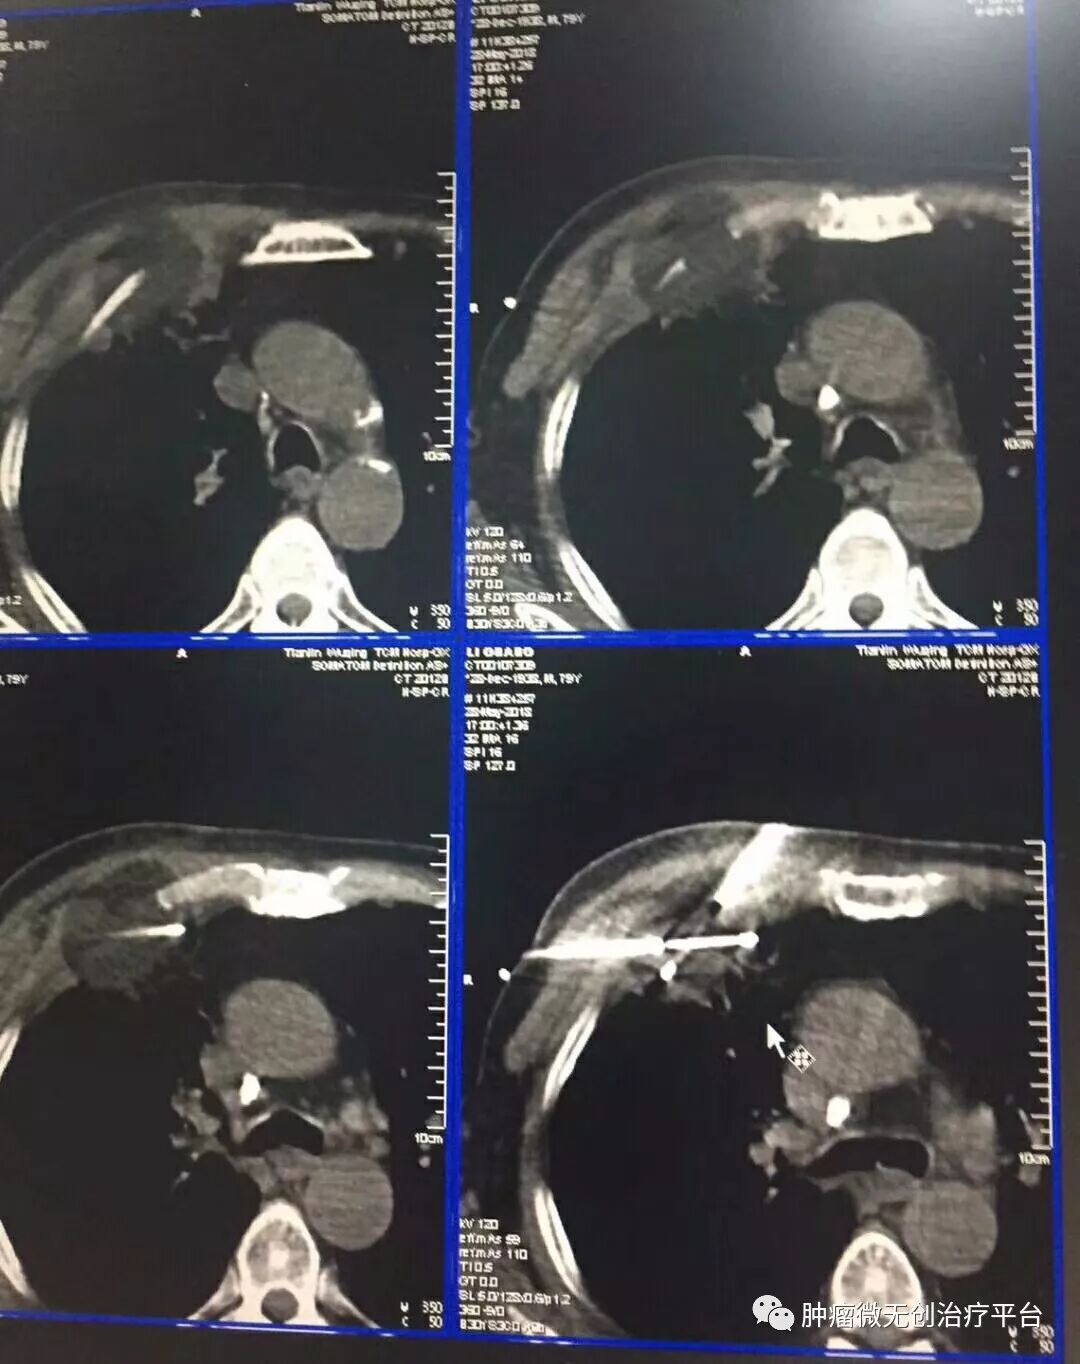

正文:5月28日,右肺腺癌侵犯胸壁患者,在天津市武清区中医医院胸外科进行氩氦刀冷冻消融治疗。

患者情况高龄(79岁)右肺腺癌侵犯胸壁患者肿瘤供血动脉栓塞➕氩氦刀冷冻消融术:图1-2术前PET-CT;图3术前CT;图4-5肿瘤供血动脉栓塞介入;图6-9氩氦刀冷冻消融治疗。